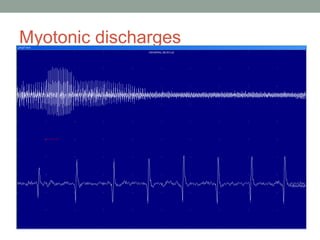

• Needle EMG: myotonic discharges are seen. Producing

characteristic dive bomber or reviving engine sound.

Myotonic discharges